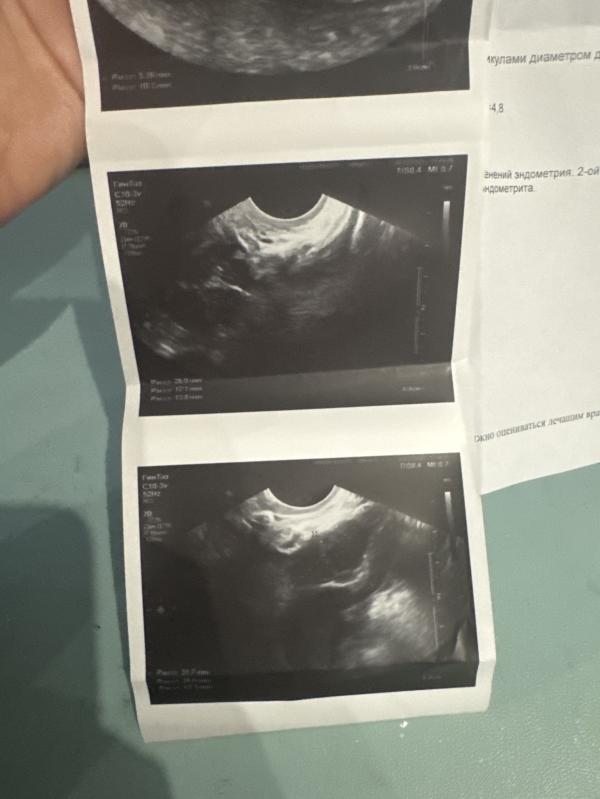

Прихожу я к ней сегодня на узи. У меня оказывается на рубце есть ниша (дырка) расслоение рубца. Что есть показание к лапороскопии. В таком состоянии нельзя беременность. Так как последствия могу быть не хорошие. И выкидыш, и разрыв матки . Нужно делать лапороскопию заново перешивать рубец. Восстановление 6-12 месяцев и уже после беременность.

И получается передняя стенка ещё очень очень маленькая. А задняя огромная

Ну и плюс ниша как дырка слева. И сам шов ещё не ровный слой